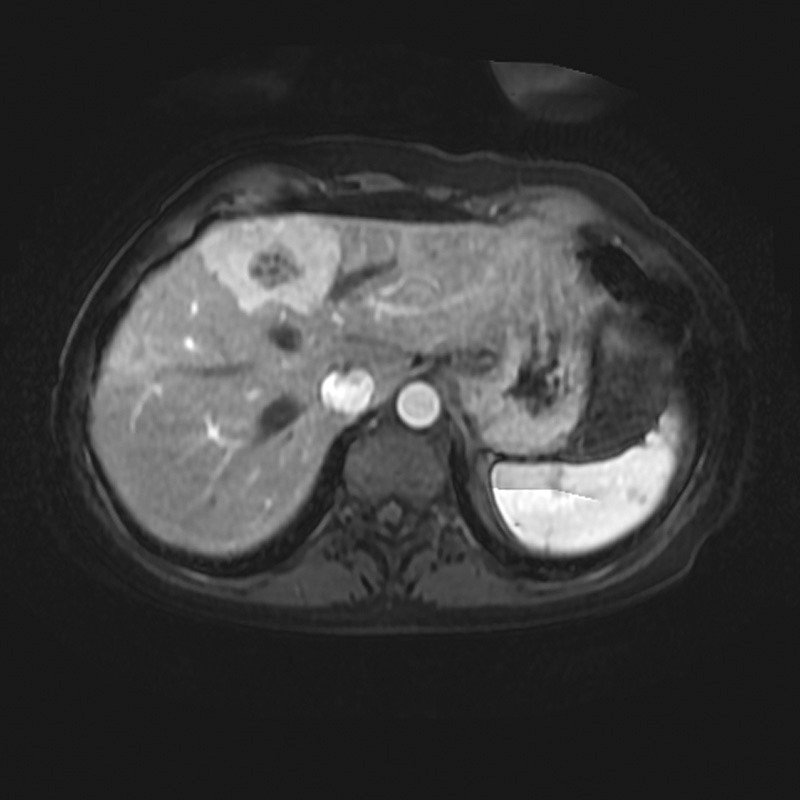

- Diaqnozu dəqiqləşdirmək üçün Qc venaları yoxlanılmalıdır. Bunun üçün dopler USM, KT-angioqrafiya, MRT-angioqrafiyalar və ya kontrastlı venoqrafiya edilir.

- Görüntüləmədə Qc venalarının trombotik tutulması diaqnozu dəqiqləşdirən əlamətdir.

Qaraciyər venalarının görünməməsi, kontrastlaşmaması və ya trombla tıxanması.

- Görüntüləmədə qaraciyər venalarının tıxanması, I seqment hipertrofiyası ola bilər (xroniki forma);